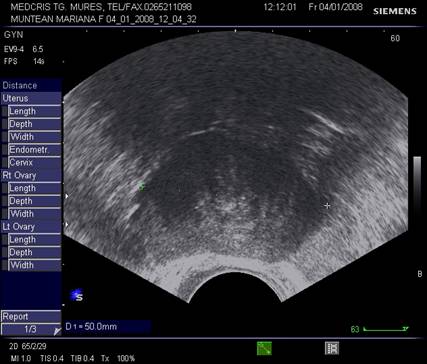

Dimensiunile uterului la o pacienta nulipara matura, masurate transvaginal sunt de 7,3 cm x 4,0 cm x 3,2 cm. In general dimensiunile cresc cu paritatea si scad dupa menopauza.

Raportul intre corp si col este aproximativ de 1,6 in ceea ce priveste lungimea.[5,6]

Endometrul - grosimea sa este apreciata in sectiune longitudinala. Masurarea se va face de la interfata miometru - endometru la interfata identica, opusa, de pe peretele celalat uterin. Maxim acceptat normal este de 1,5 cm in perioada de premenopauza.[5] Postmenopauza in mod normal nu depaseste 5 mm, de obicei este atrofic si apare ca o imagine ecogena lineara. Daca apare o colectie anecogena postmenopauzala intrauterina, prin atrofie cervicala, aceasta colectie nu trebuie sa fie masurata la calculul grosimii endometriale.[2,6]